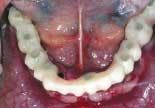

The patient is a 50-year-old male who is in good general health (figure 1). His chief complaint was the deterioration of his lower teeth (figure 2). He has been wearing a complete upper denture for about 20 years. His desire was to have fixed teeth in both the upper and lower arches.

On the day of surgery, the remaining lower teeth are extracted (figure 3) and alveoplasty performed. Branemark Mk III TiU implants were placed in the 37, 36, 34, 44, 46, 47, and 31 sites. Branemark RS TiU implants were placed in the 43 and 33 sites. All implants were torqued to 45 Ncm. Multi-unit abutments were placed on the implants and torqued to 35 Ncm (figure 4). Bioss 1:1 autogenous grafting was done in the anterior region (figure 5) and the sites closed with chromic gut sutures. The maxillary CUD was inserted and the CLD was modified and relined with tissue conditioner.